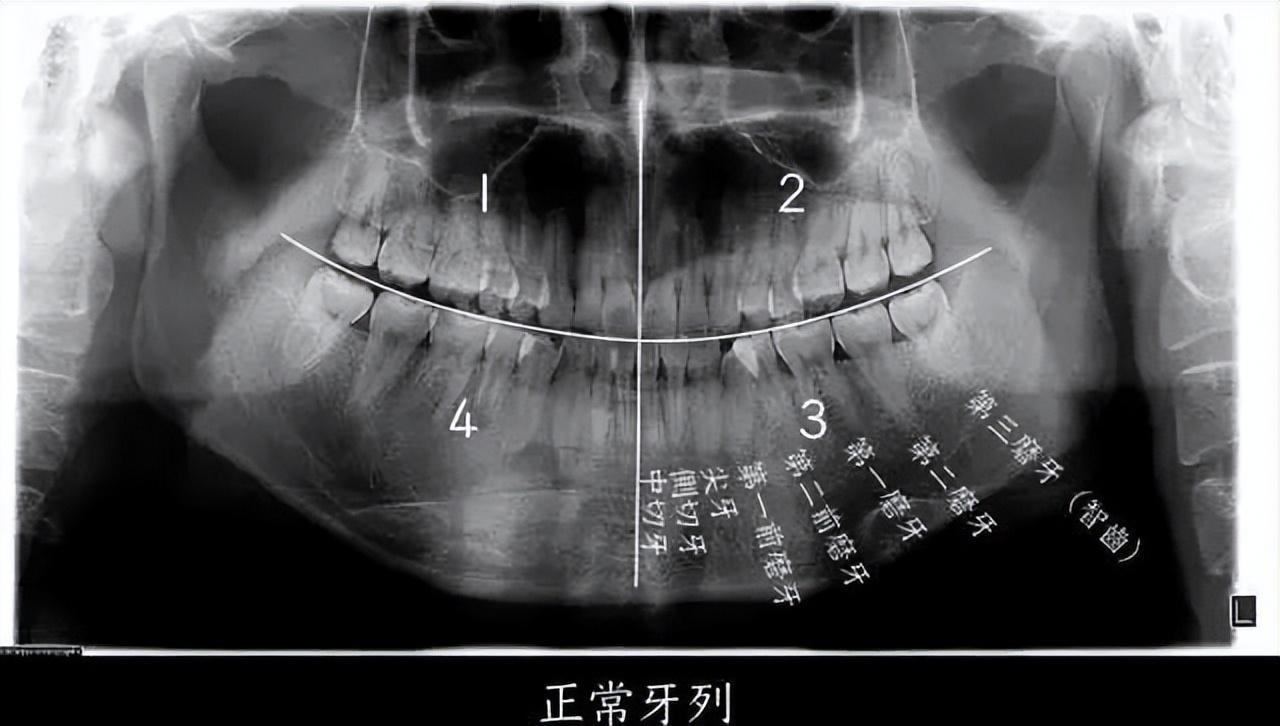

什么是智齿?

要问拔不拔,先问有没有!

并非所有人都一定长有智齿

通常,一个成年人长出28~32个牙齿都是正常的,不排除有的人没有长智齿,且也不存在智齿。

▲智齿即第三磨牙,位于口腔最远最深位置

如果把一个正常成年人的口腔分为左上、左下、右上、右下四个区域的话,每个区域会有8个牙齿,长在最后的第8颗牙齿,就是我们口中的“智齿”,即第三磨牙。